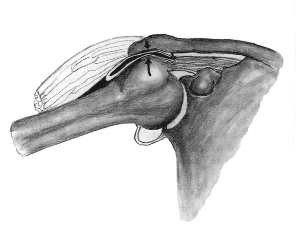

The tendon of the rotator cuff and bursa (between the tendon and the acromion) slide between the humeral head and the acromion during an upward movement of the upper arm.

If there is a hooked acromion or a very thick band (ligament coracoacromial) between the ball (acromion) and coracoid, then there is insufficient space for the tendon and bursa to slide between the humeral head and the acromion.

It comes to the so-called impingement, that is the entrapment of the soft tissues between the humeral head and the acromion.

Impingement of the tendon and bursa when lifting the arm.